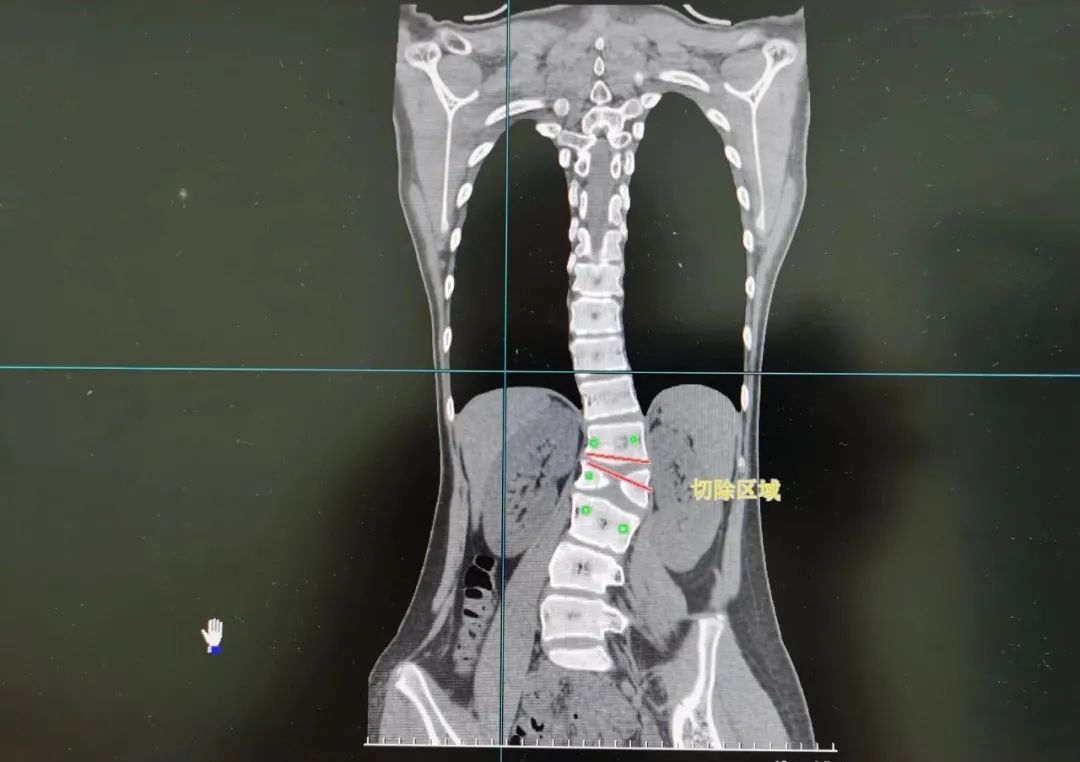

8月12日,经过充分的术前准备后,由王达义教授主刀,带领团队为小梦开展截骨矫形手术。王达义教授在先进的神经监护仪器的监护下,使用“切骨如切豆腐”的超声骨刀,根据术前计算标记好的截骨角度及节段,精准切除发育畸形的部分脊椎骨。

术后复查 CT显示,小梦原本畸形的腰椎得到彻底纠正。